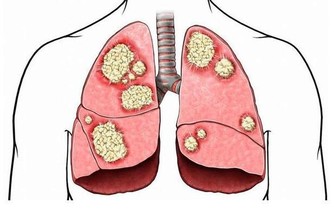

不吃早餐比空腹喝水傷害更大,早餐要吃好吃對

不吃早餐最直接的就是會傷害胃部健康。經過一夜的分解、消化,此時的胃酸濃度很高,而如果不吃早餐,飢餓就會使得胃酸持續分泌長期不吃早餐會造成胃酸持續傷害胃黏膜,很容易出現胃炎、胃潰瘍等腸胃疾病。